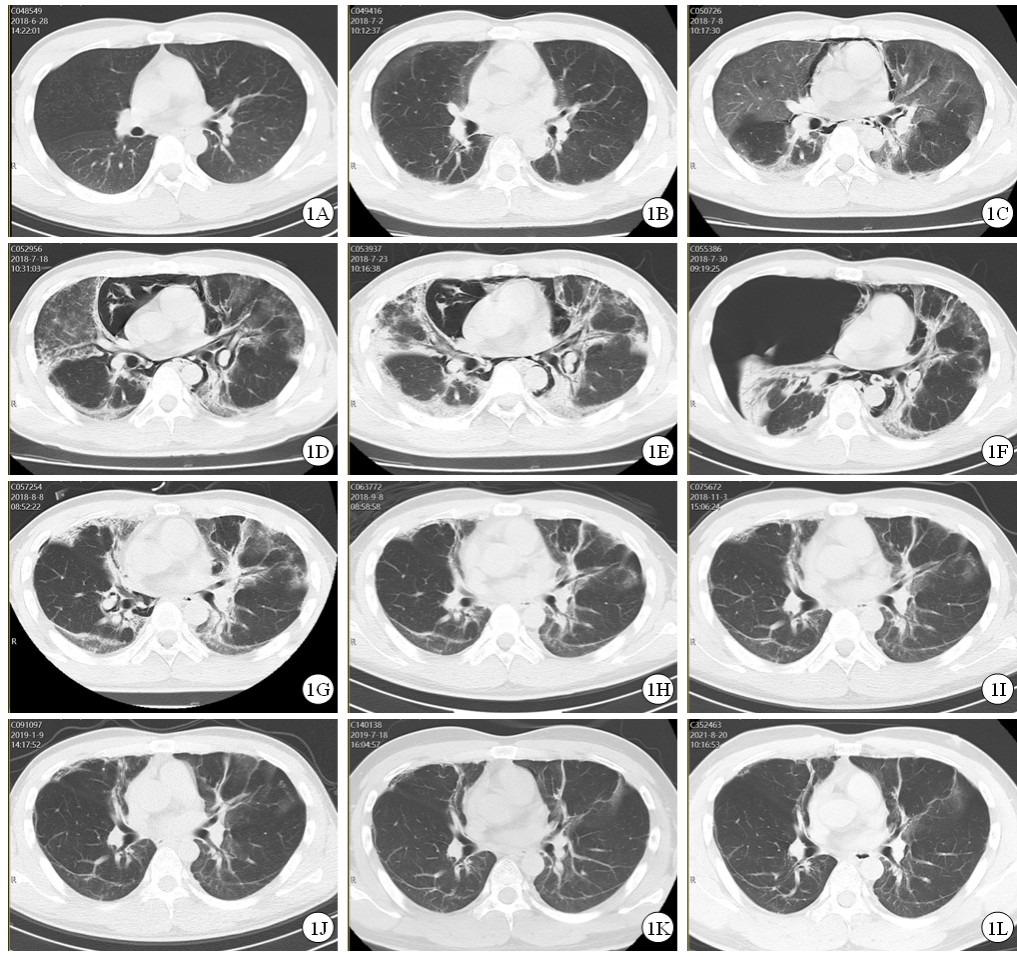

治疗效果:患者治疗过程中给予持续心电监护、血氧饱和度监测、血压监测、记出入量,动态监测肝肾功能变化(表 1)。入院12 h后尿液中PQ含量降至10~30 mg/L,入院18 h后尿液中PQ含量降至0~3 mg/L。入院第2天出现口腔黏膜充血,咽部疼痛,血肌酐升高,PaCO2: 35mmHg,PaO2:115 mmHg,Lac: 3.9 mmol/L;第3天出现顽固性呃逆,间断予以氯丙嗪肌肉注射,PaO2: 103 mmHg,Lac: 4.5 mmol/L,胸部CT:双肺下叶条索灶(图 1A);第5天口咽黏膜糜烂疼痛加重,全身皮肤黏膜黄染,肝功能相关指标明显升高,PaO2: 92 mmHg,Lac: 1.5 mmol/L;第7天未再出现呃逆,PaO2: 90 mmHg,Lac: 1.4 mmol/L,胸部CT:双肺间质性改变,双侧胸腔积液(图 1B);第12天肾功能相关指标恢复正常,肝功能相关指标开始好转,PaO2: 63 mmHg;第13天胸部CT:纵隔、颈部及胸壁气肿,双肺间质纤维化范围较前增大,双侧胸腔少量积液(图 1C);第23天口咽部疼痛明显减轻,PaO2: 74 mmHg,胸部CT:纵隔气肿及皮下气肿较前加重,双肺间质弥漫磨玻璃样影及条索状高密度灶较前密度增高,肺组织较前膨胀不全,双侧胸腔仍见少量积液(图 1D);第28天胸部CT示纵隔气肿及皮下气肿、双肺间质性肺炎并纤维化、肺组织膨胀不全较前较前持续加重(图 1E);第31天肝功能相关指标恢复正常;第35天患者突发胸闷憋气,胸部CT示右侧大量气胸、纵隔偏移(图 1F),急症行胸腔闭式引流术后,症状缓解;第42天PaO2: 87 mmHg,胸部CT示右侧胸膜腔及纵隔内气体较前明显减少,双肺间质弥漫磨玻璃样影及条索状、斑片状高密度灶较前减轻(图 1G);第44天出院。服毒半年后,患者自述无胸闷、憋气、胸痛等不适,步行上五楼无明显气促症状,PaO2: 76 mmHg,胸部CT:双肺间质弥漫磨玻璃样影及条索状、斑片状高密度灶,范围较前缩小,边缘较前清晰(图 1J)。服毒1年后,患者可从事正常体力劳动,PaO2: 91 mmHg,胸部CT: 双肺野内示多发纤维条索灶,胸膜下线形成,肺纤维化复查好转CT表现(图 1K)。服毒3年后,患者已从事正常体力劳动,PaCO2: 39 mmHg,PaO2: 82 mmHg,胸部CT:双肺野内示多发纤维条索灶,胸膜下线形成,较前未见明显变化(图 1L)。